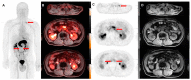

Metastatic castration-resistant prostate cancer (mCRPC) represents a condition of progressive disease in spite of androgen deprivation therapy (ADT), with a broad spectrum of manifestations ranging from no symptoms to severe debilitation due to bone or visceral metastatization. The management of mCRPC has been profoundly modified by introducing novel therapeutic tools such as antiandrogen drugs (i.e., abiraterone acetate and enzalutamide), immunotherapy through sipuleucel-T, and targeted alpha therapy (TAT). This variety of approaches calls for unmet need of biomarkers suitable for patients' pre-treatment selection and prognostic stratification. In this scenario, imaging with positron emission computed tomography (PET/CT) presents great and still unexplored potential to detect specific molecular and metabolic signatures, some of whom, such as the prostate specific membrane antigen (PSMA), can also be exploited as therapeutic targets, thus combining diagnosis and therapy in the so-called "theranostic" approach. In this review, we performed a web-based and desktop literature research to investigate the prognostic and theranostic potential of several PET imaging probes, such as 18F-FDG, 18F-choline and 68Ga-PSMA-11, also covering the emerging tracers still in a pre-clinical phase (e.g., PARP-inhibitors' analogs and the radioligands binding to gastrin releasing peptide receptors/GRPR), highlighting their potential for defining personalized care pathways in mCRPC.